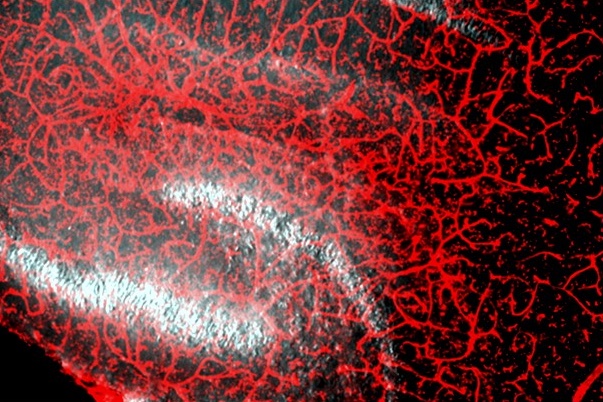

Prof David Attwell with an image of brain blood vessel Credit: Prof David Attwell

Just like a computer, the brain needs a supply of energy, which arrives in the blood as glucose and oxygen. In both Alzheimer’s disease and vascular dementia, the brain’s energy supply is reduced by a decrease of blood flow. For human Alzheimer’s disease (and a mouse model of it), the Attwell Lab has shown that this is caused by constriction of the smallest blood vessels - capillaries - by tiny muscle cells (called pericytes) that wrap around the capillaries.

The Attwell Lab are interested in how a fall of cerebral blood flow (CBF), a possibly downstream decrease of blood-brain barrier (BBB) function and demyelination, contribute to vascular dementia and Alzheimer’s disease (AD). These are all early changes in the sequence of events leading to dementia, which may offer opportunities for prophylaxis or early treatment. The team have previously shown that constriction of brain capillaries by pericytes can reduce cerebral blood flow by 50% (as seen in AD), and that this can be mediated by amyloid beta evoking production of reactive oxygen species which release the vasoconstrictor endothelin-1. The resulting capillary constriction can be reversed by agents that raise cyclic nucleotide (cAMP and cGMP) levels or block L-type Ca2+ channels. These approaches may be useful adjuncts to lowering amyloid beta level using antibodies.